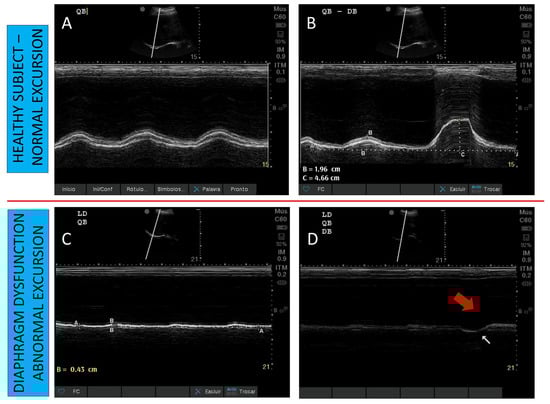

4.2.1. To Diagnose Diaphragmatic Dysfunction

- Goligher, E.C.; Laghi, F.; Detsky, M.E.; Farias, P.; Murray, A.; Brace, D.; Brochard, L.J.; Bolz, S.S.; Rubenfeld, G.D.; Kavanagh, B.P.; et al. Measuring diaphragm thickness with ultrasound in mechanically ventilated patients: Feasibility, reproducibility and validity. Intensive Care Med. 2015, 41, 642–649. [Google Scholar] [CrossRef]

- Matamis, D.; Soilemezi, E.; Tsagourias, M.; Akoumianaki, E.; Dimassi, S.; Boroli, F.; Richard, J.C.; Brochard, L. Sonographic evaluation of the diaphragm in critically ill patients. Technique and clinical applications. Intensive Care Med. 2013, 39, 801–810. [Google Scholar] [CrossRef]

- Santana, P.V.; Cardenas, L.Z.; de Albuquerque, A.L.P.; de Carvalho, C.R.R.; Caruso, P. Diaphragmatic ultrasound: A review of its methodological aspects and clinical uses. J. Bras. Pneumol. 2020, 46. [Google Scholar] [CrossRef]

- Haaksma, M.E.; Smit, J.M.; Boussuges, A.; Demoule, A.; Dres, M.; Ferrari, G.; Formenti, P.; Goligher, E.C.; Heunks, L.; Lim, E.H.T.; et al. EXpert consensus On Diaphragm UltraSonography in the critically ill (EXODUS): A Delphi consensus statement on the measurement of diaphragm ultrasound-derived parameters in a critical care setting. Crit. Care 2022, 26, 99. [Google Scholar] [CrossRef]

- Tuinman, P.R.; Jonkman, A.H.; Dres, M.; Shi, Z.H.; Goligher, E.C.; Goffi, A.; de Korte, C.; Demoule, A.; Heunks, L. Respiratory muscle ultrasonography: Methodology, basic and advanced principles and clinical applications in ICU and ED patients—A narrative review. Intensive Care Med. 2020, 46, 594–605. [Google Scholar] [CrossRef]

- Zambon, M.; Greco, M.; Bocchino, S.; Cabrini, L.; Beccaria, P.F.; Zangrillo, A. Assessment of diaphragmatic dysfunction in the critically ill patient with ultrasound: A systematic review. Intensive Care Med. 2017, 43, 29–38. [Google Scholar] [CrossRef]

- Boussuges, A.; Gole, Y.; Blanc, P. Diaphragmatic motion studied by m-mode ultrasonography: Methods, reproducibility, and normal values. Chest 2009, 135, 391–400. [Google Scholar] [CrossRef] [PubMed]

- Testa, A.; Soldati, G.; Giannuzzi, R.; Berardi, S.; Portale, G.; Silveri, N.G. Ultrasound M-mode assessment of diaphragmatic kinetics by anterior transverse scanning in healthy subjects. Ultrasound Med. Biol. 2011, 37, 44–52. [Google Scholar] [CrossRef]

- Schepens, T.; Fard, S.; Goligher, E.C. Assessing diaphragmatic function. Respir. Care 2020, 65, 807–819. [Google Scholar] [CrossRef] [PubMed]

- Lerolle, N.; Guérot, E.; Dimassi, S.; Zegdi, R.; Faisy, C.; Fagon, J.Y.; Diehl, J.L. Ultrasonographic diagnostic criterion for severe diaphragmatic dysfunction after cardiac surgery. Chest 2009, 135, 401–407. [Google Scholar] [CrossRef]

- Boon, A.J.; Harper, C.J.; Ghahfarokhi, L.S.; Strommen, J.A.; Watson, J.C.; Sorenson, E.J. Two-dimensional ultrasound imaging of the diaphragm: Quantitative values in normal subjects. Muscle Nerve 2013, 47, 884–889. [Google Scholar] [CrossRef]